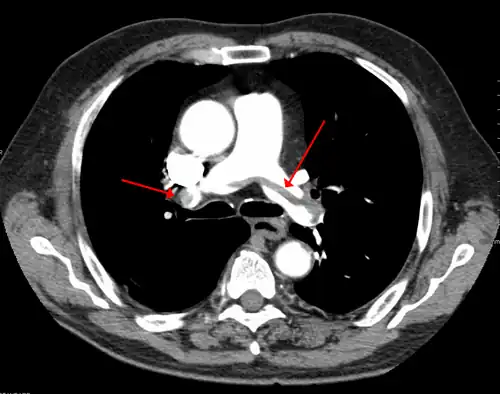

- A CT image with red arrows indicating PE (grey) in the pulmonary arteries (white)

-